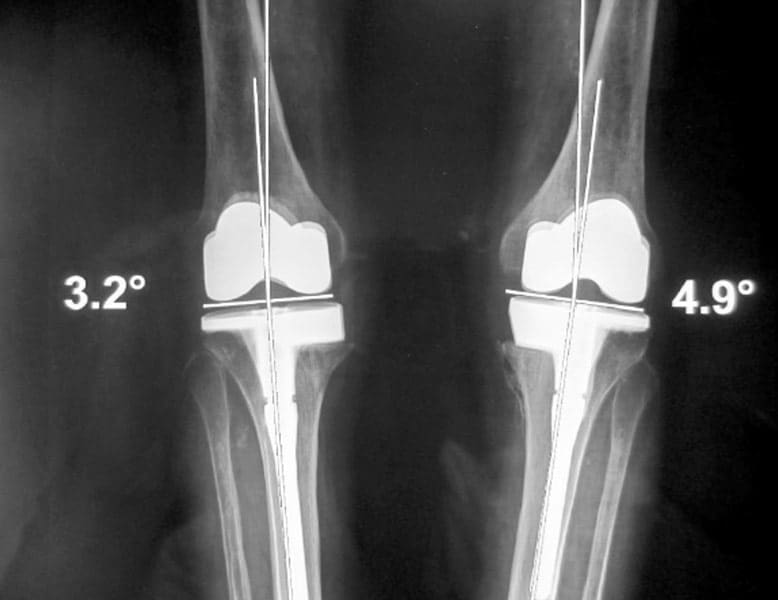

Déformation du genou en valgus (jambes en X), femme jeune (45 ans), ancienne handballeuse aux jeux de Séoul ; le fémur et le tibia sont déformés. Handicap majeur.

On réalise une double ostéotomie de varisation lors de la même opération, fémorale et tibiale, fixées avec des agrafes métalliques.